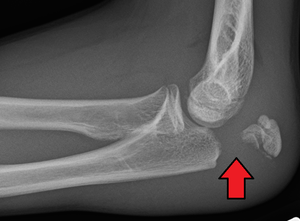

Olecranon fracture is a fracture of the bony portion of the elbow. The injury is fairly common and often occurs following a fall or direct trauma to the elbow. The olecranon is the proximal extremity of the ulna which is articulated with the humerus bone and constitutes a part of the elbow articulation. Its subcutaneous location makes it vulnerable to direct trauma. Powerful pull of the triceps muscle can also cause avulsion fractures.

Frontal and lateral X-ray views of the elbow are typically done to investigate the possibility of an olecranon fracture. A standard lateral view of the elbow insufficient to diagnose olecranon fractures. A true lateral x-ray is essential to determine the fracture pattern, degree of displacement, comminution, and the degree of articular involvement.